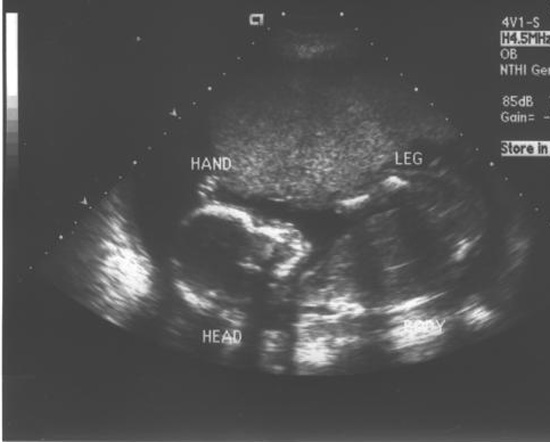

My great nephew, Aiden Michael, will arrive in a little over four months.